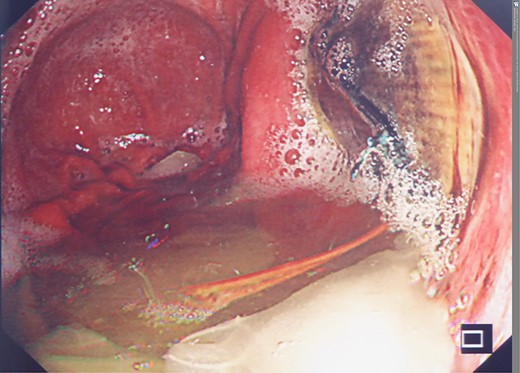

However, 4 and a half months later he again became haemodynamically unstable with a further episode of haematemesis. A further CT angiogram showed contrast entering the neo-oesophagus from the thoracic aorta (Fig. 5). The patient was again taken to the emergency theatre and the previous stent was relined with further stents extending both proximally and distally beyond the previous stent, with care taken not to occlude the celiac trunk and arteries below this (Cook Medical ZTA-26-105 and Cook Medical ZTA-28-109). Again, the patient had a quick recovery. However, repeat endoscopy showed that the aortic stent was visible through a defect in the wall of the neo-oesophagus (Fig. 6).

Second admission: OGD post second stent insertion demonstrating visibility of aortic stent via defect in wall of neo-oesphagus.